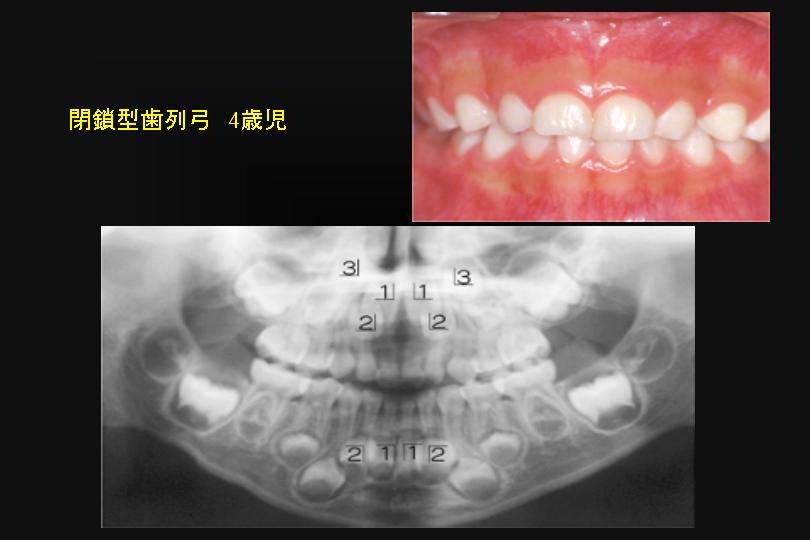

ところで切端咬合の乳歯前歯には空隙がある小児が多い。

4歳児の乳歯空隙歯列弓のパノラマレントゲン撮影を行うと、下顎の永久4前歯は顎骨内で並列になっており、

永久歯はきれいな歯列になることは容易に想像できる。(図5)

図5

図5:乳歯の切端咬合は、空隙歯列弓が多い。